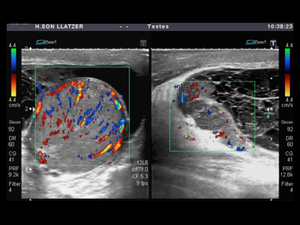

- Ultrasonido testicular. Para descartar la torsión testicular puede usarse esta prueba de diagnóstico por imágenes. El ultrasonido Doppler a color puede determinar si el flujo sanguíneo a los testículos es menor de lo normal, lo que indica torsión, o mayor de lo normal, lo que ayuda a confirmar el diagnóstico de orquitis.